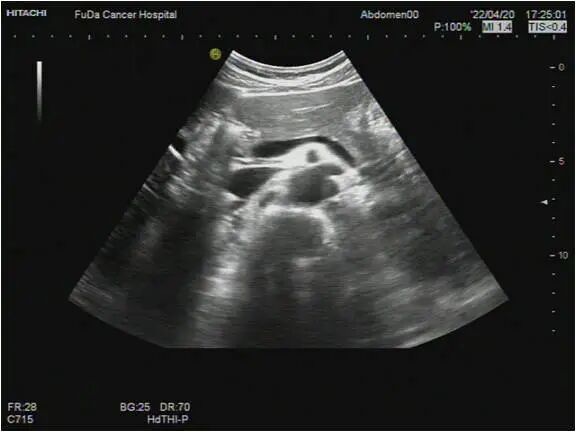

51959 篇文章 0 次评论夫妻二人相继患胰腺癌,不沾烟酒!医生:不想胰腺出问题,4类食物要少吃